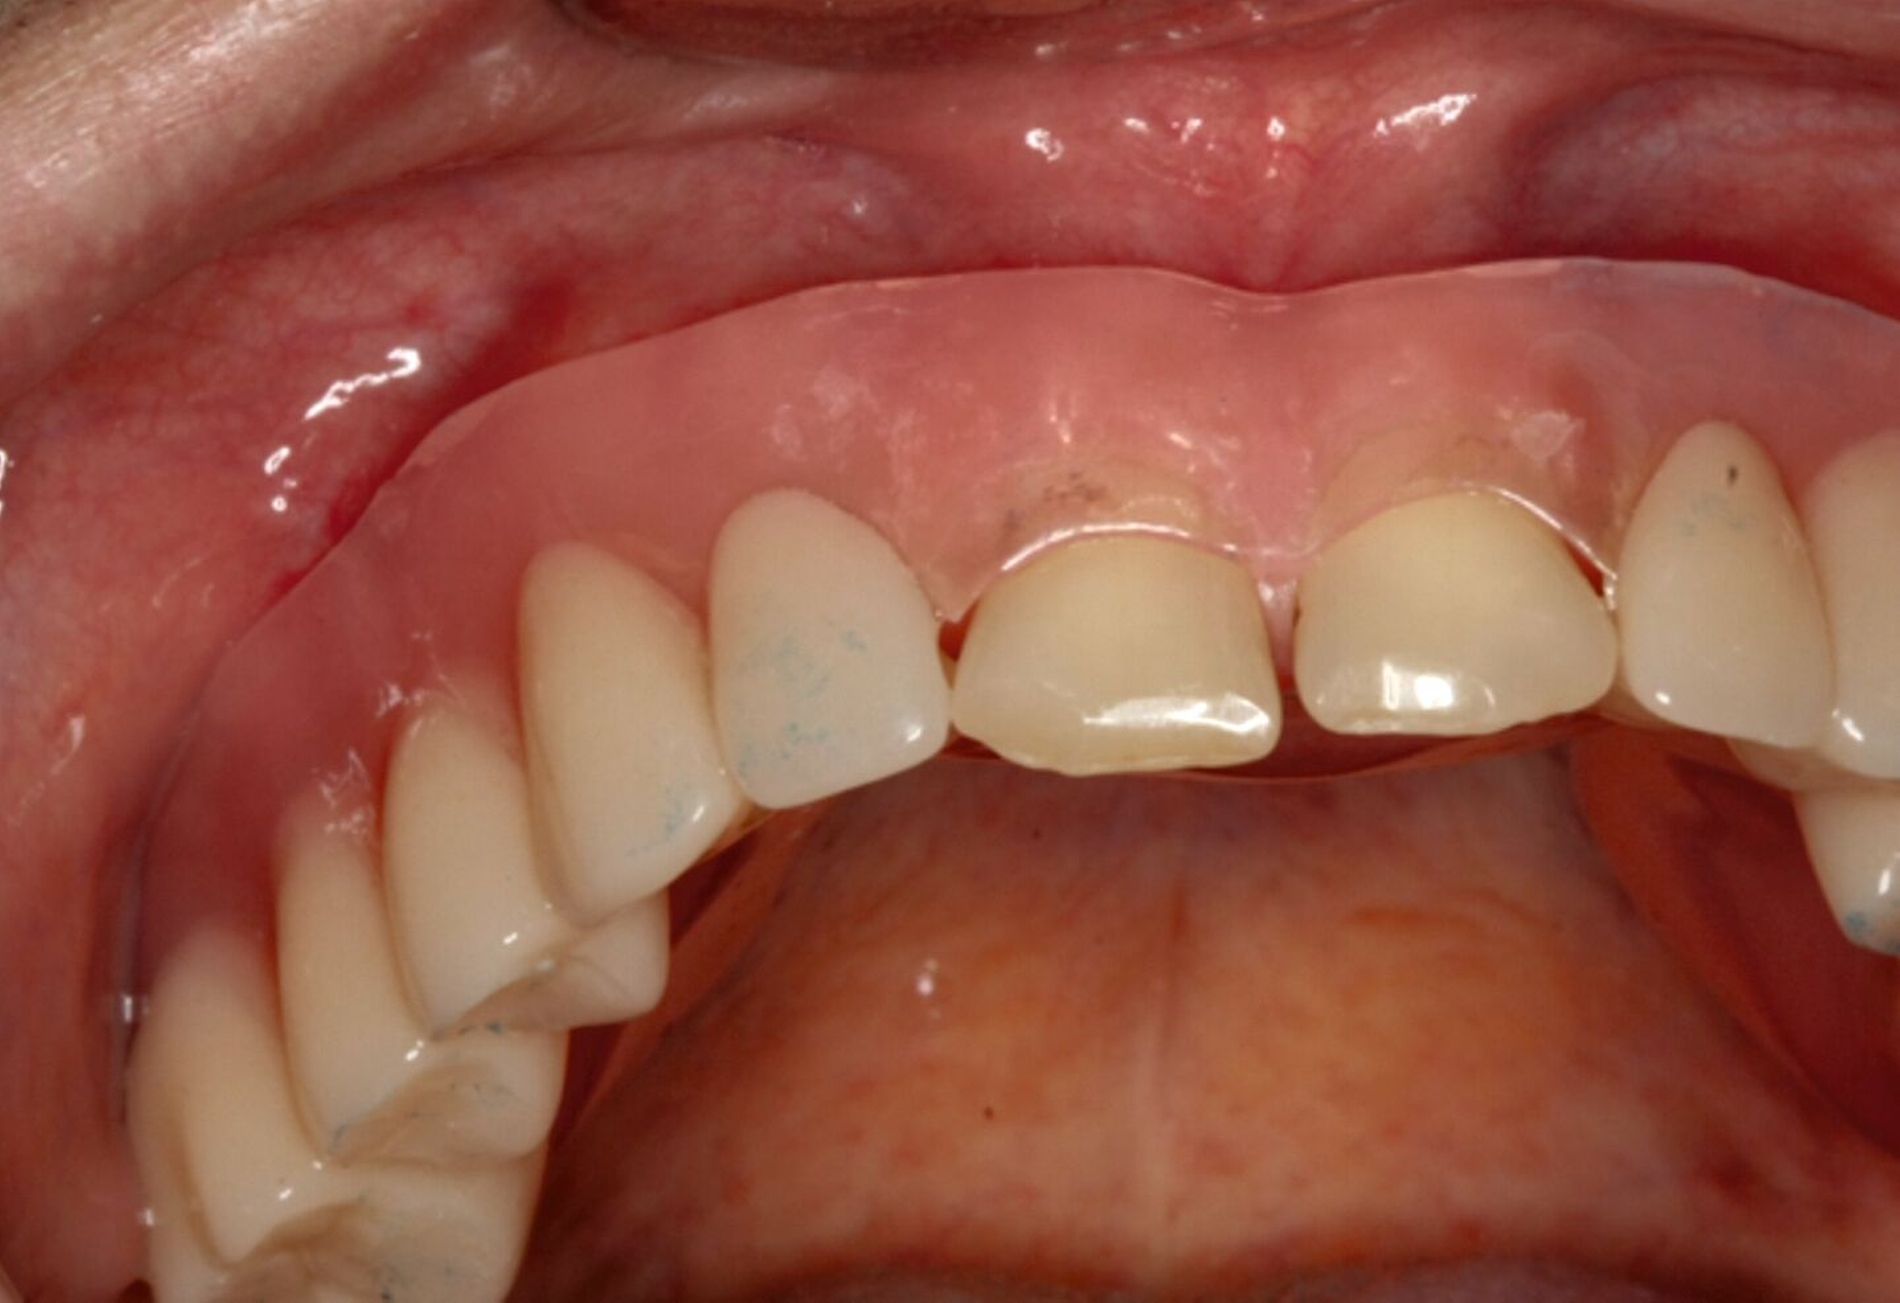

Eine mögliche und indizierte Umstellungsosteotomie wurde vom Patienten abgelehnt. Da seitens des Patienten eine Kopfbissstellung möglich war, wurde eine Bissumstellung und -hebung mit nur noch geringgradigem Vorbiss und anschließender Zahnimplantation in Erwägung gezogen. Begonnen wurde mit einer temporären Schienentherapie zur Neuorientierung der Bisslage (Abbildung 3). Da der Patient die angepasste Bisshebung tolerierte, wurde diese nach Entfernung der persistierenden Milchzähne 55, 53, 52, 62 und 83 temporär mittels einer Valplastprothese (Abbildung 4) als Interimsersatz im Oberkiefer gesichert.

Im Oberkiefer: Implantationen zur Pfeilervermehrung und Teleskopversorgung, alternativ festsitzende Kronen-Brückenversorgungen. Eine Teleskopversorgung allein auf den restlichen natürlichen Zähnen wäre aufgrund der vertikalen Distanz nach erforderlicher Bisshebung nicht möglich gewesen.

Im Unterkiefer: Lückenschluss mit konventionellen Brückenversorgungen mit fraglicher Prognose, alternativ Einzelzahnimplantationen mit Implantatkronen.

Kronenverlängerungen und Überkronungen der teilretinierten Zähne 16 und 26.